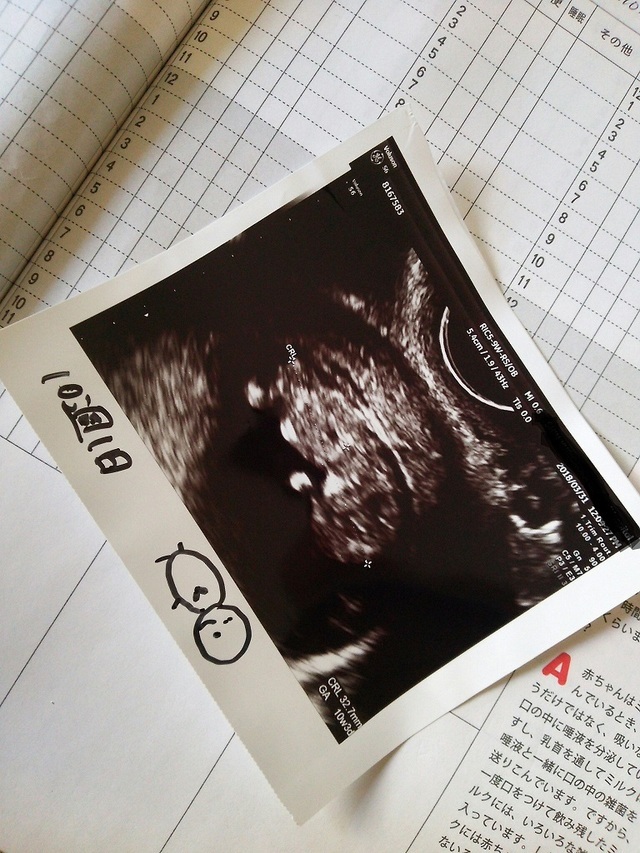

10週3日(10w3d・性別不明)|なぁひろ さん(20歳)

エコー写真撮影時のエピソード:

前回卵みたいな形だったのが初めて頭や足が見えて、ちゃんと成長したのが目に見えて分かって、愛おしく思えた。鉄分を取るようにしたり、葉酸のタブレットを買ったり、好きだったお寿司や生物を食べないように気をつけるようになった。パパもエコー写真を見て父親の自覚が出てきた。